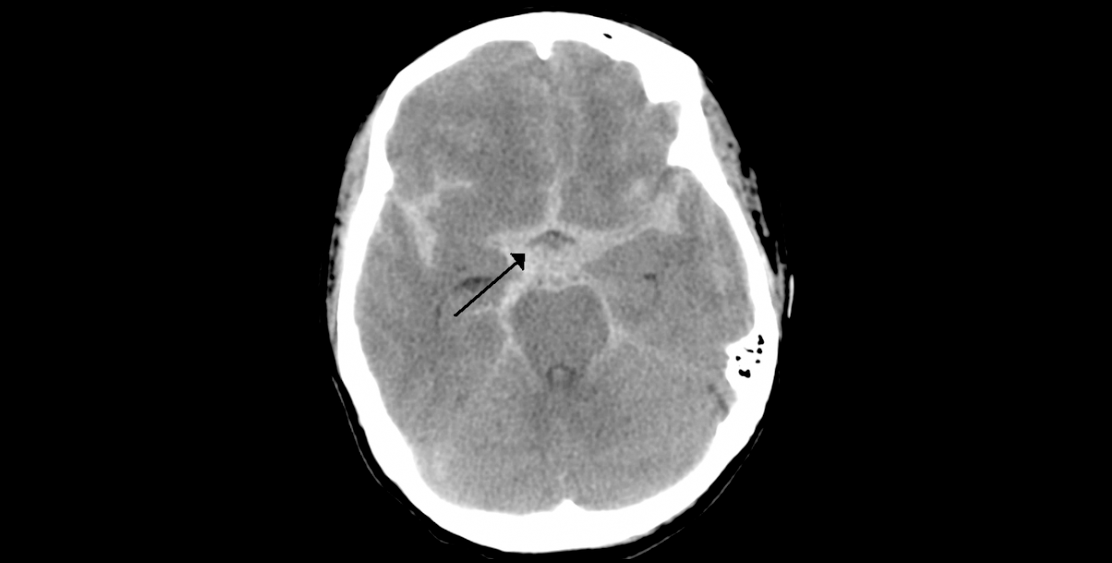

Subarachnoid hemorrhage

Data on subarachnoid hemorrhage

Wikipedia. (n.d.). Subarachnoid hemorrhage [Computed axial tomography]. Retrieved from https://en.wikipedia.org/wiki/Subarachnoid_hemorrhage

This type of hemorrhage is related to excessive alcohol consumption, smoking and HBP, in addition to representing an increased risk of SAH for women (Barinagarrementeria and Cantú, 2003).